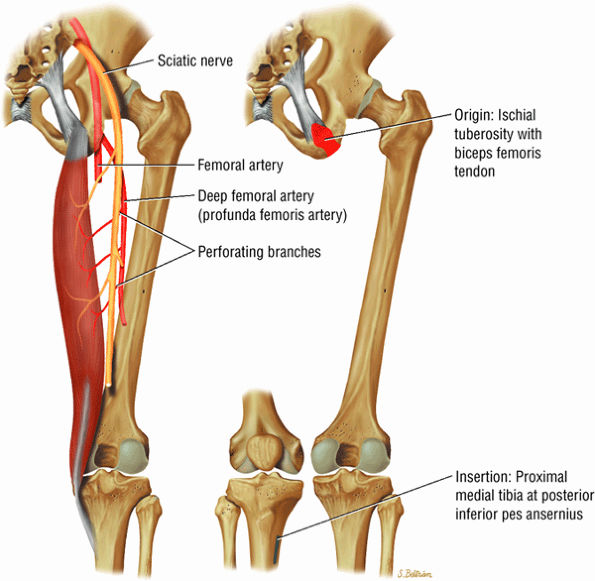

FIGURE 3.31 / Femur and Acetabulum.